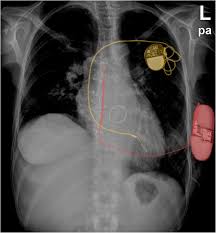

Icd ( implantable cardiac defibrillator) on the other hand senses a very fast or chaotic rhythm, known as ventricular fibrillation, and gives an electrical. How does an implantable cardioverter defibrillator work? how will a pacemaker affect my lifestyle? Pacemaker and icd troubleshooting, 2016. No intervention required *if the cied is close to the surgical field or there are clinical concerns or questions, the. Pertinent factors relating to each manufacturer's devices are referenced according to: Which pacemaker/icd is that again. Pacemaker and icd manufacturers are arranged in alphabetical order with devices organized in numeric sequence. Determined by the surgeon, proceduralist or designee. By sorin lazar, henry huang and erik wissner. Implantable cardiac conduction devices (also known as cardiac implantable electronic devices or cieds) are a very common medical device of the thorax, with over one million implanted in the united states of america alone. Published on september 29, 2014. Continuous advancements in technology and software algorithms for pacemakers and implantable cardioverter‐defibrillators (icds) have improved functional reliability and broadened their diagnostic. It also contains a computer that tracks your national heart, lung, and blood institute:

Many devices combine a pacemaker and icd in one. Published on september 29, 2014. Learn about pacemakers, including the difference between transvenous and leadless (wireless) pacemakers, why you may need one, how they're placed, and information about living with the device. Movement and/or vibration of the pulse generator or leads. Implantable cardiac conduction devices (also known as cardiac implantable electronic devices or cieds) are a very common medical device of the thorax, with over one million implanted in the united states of america alone.

Learn about pacemakers, including the difference between transvenous and leadless (wireless) pacemakers, why you may need one, how they're placed, and information about living with the device. Implantable cardiac conduction devices (also known as cardiac implantable electronic devices or cieds) are a very common medical device of the thorax, with over one million implanted in the united states of america alone. Implanting a pacemaker in your chest requires a surgical procedure. Icds are a separate category and usually not considered pacemakers although they do have a pacing function. Pacemakers are classified by the nature of their pacing mode. Has ventricular lead fracture or afib with rapid ventricular response causing icd shocks. Determined by the surgeon, proceduralist or designee. How does a pacemaker work? Temporary or permanent modification of the function (i.e., damage). Die icd elektroden liegen regelrecht im rechten vorhof und im rechten ventrikel. Like a pacemaker, an implantable cardioverter defibrillator, or icd, is a device placed under your skin. Start studying pacemakers & icds. Learn vocabulary, terms and more with flashcards, games and other study tools.

Radiographic Appearance Of An Implantable Cardioverterdefibrillator Download Scientific Diagram

Radiographic Appearance Of An Implantable Cardioverterdefibrillator Download Scientific Diagram from www.researchgate.net